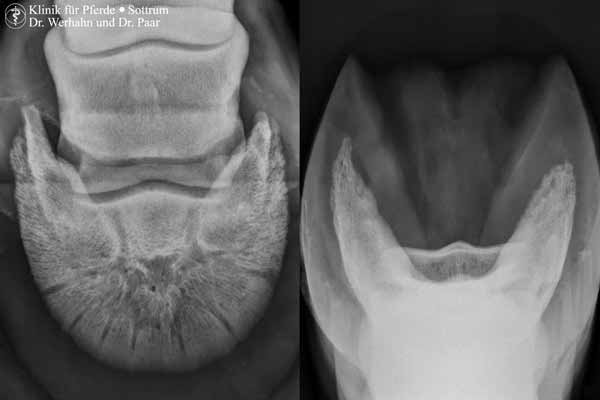

Neben den Standardaufnahmen im unteren Gliedmaßenabschnitt ist somit auch die röntgenologische Untersuchung von Ellbogengelenk, Schulter, Knie und Hüftgelenk, Halswirbelsäule, Rücken sowie von Kopf und Zähnen in sehr guter Qualität und unter Berücksichtigung der Anforderungen des Strahlenschutzes für die exponierten Personen möglich.

Aber neben der apparativen Ausstattung machen nicht zuletzt die Exaktheit bei der Röntgenbilderstellung, die Genauigkeit bei der Befunderhebung und die Fähigkeit und das Wissen zur Beurteilung von Röntgenbildern den Wert einer röntgenologischen Untersuchung aus. Auch durch die konsequente Ausnutzung von Spezialprojektionen wird der Nutzen der röntgenologischen Untersuchung deutlich erhöht. So können häufig die Kosten für die aufwendigeren bildgebenden Verfahren gespart werden.